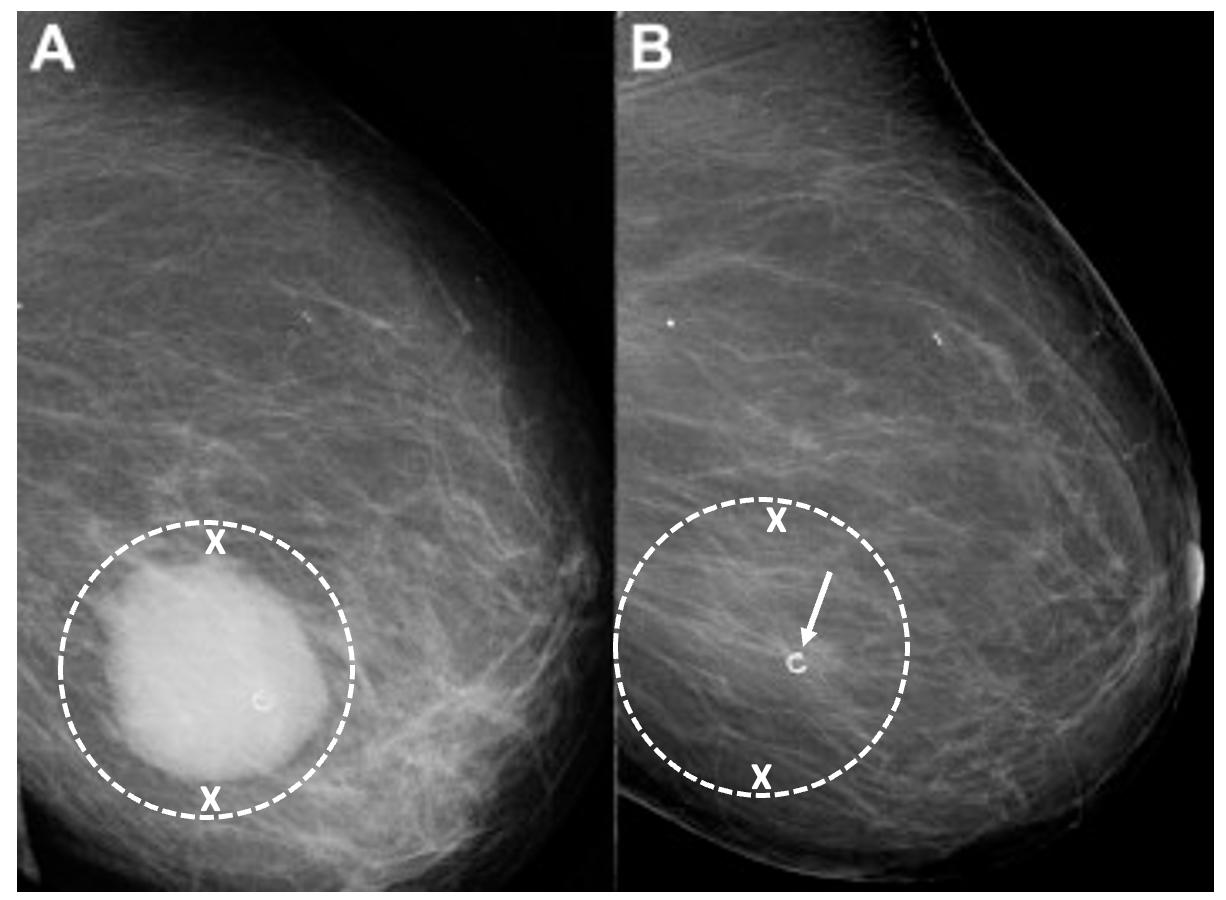

Placement of biopsy site marker(s). Regardless of cancer size, insertion of a biopsy site marker (also called a “clip” or “chip”) at the time of mammogram-, ultrasound-, or MRIguided needle biopsy is recommended to document the site of the cancer. In situations where pre-cryoablation chemotherapy and/or anti-HER2/neu therapy is planned, insertion of a biopsy site marker prior to initiation of anticancer medications documents the location of the cancer in the event drug therapy-induced shrinkage of the cancer makes it difficult to detect by ultrasound (Image 5).

Image 5. Mammogram performed before (A) pre-operative chemotherapy showing large, white, ultrasound visible cancer encircled by hash marks. After completing pre-operative chemotherapy, a repeat mammogram (B) of the same breast showed complete disappearance of the original cancer leaving only a circular metal biopsy site marker (arrow) to indicate the location of the original cancer.